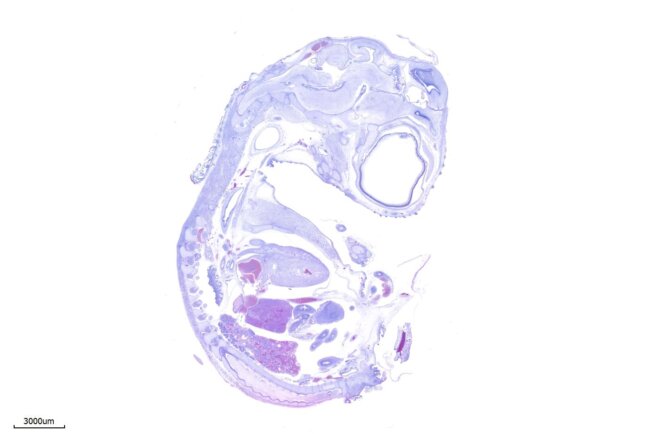

HE染色